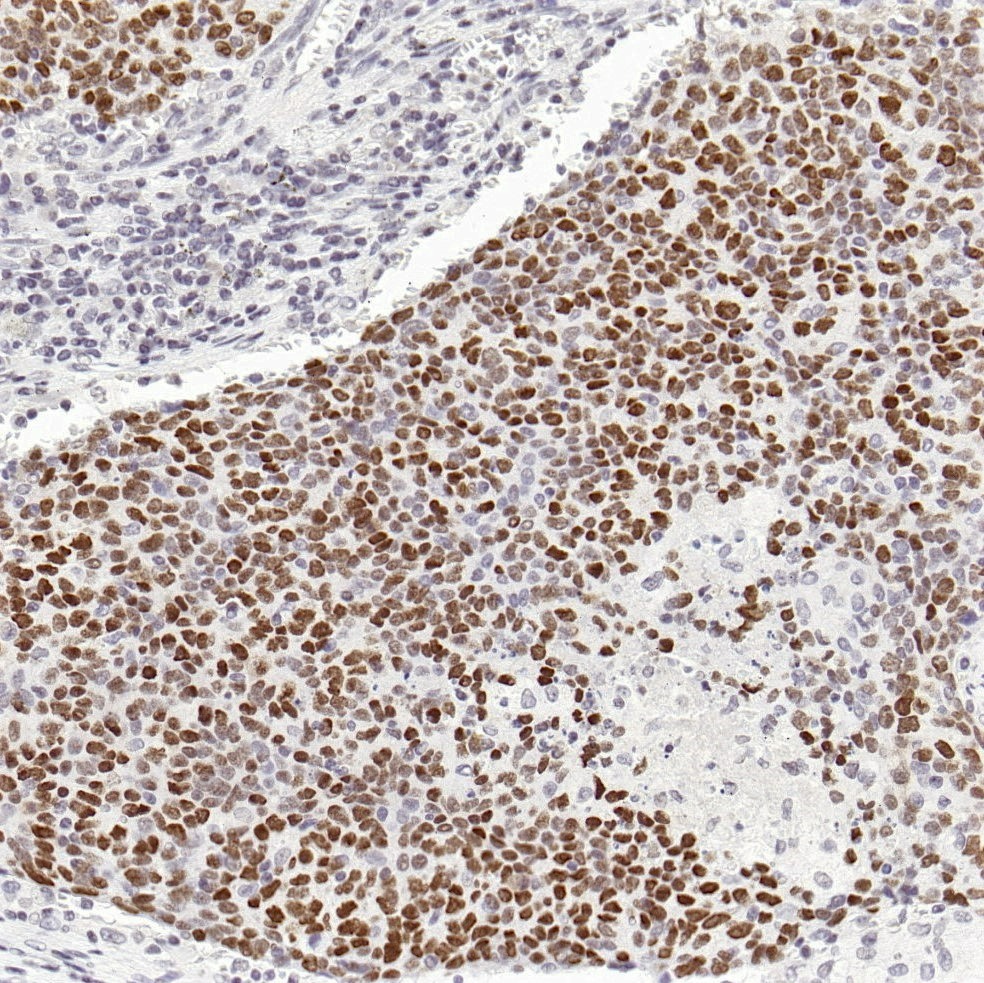

鼻咽癌EBER探针染色

肺癌EBER探针染色

伯基特淋巴瘤EBER染色

EB病毒是一种嗜淋巴细胞疱疹病毒,被国际癌症研究署列为致癌因子之一。EBER是EB病毒编码的小mRNA产物,存在于EB病毒潜伏期、复制期等各个时期。原位杂交检测EBERs能够定位EBV感染的细胞类型,是明确肿瘤与EBV相关的金标准。百凌生物全新推出EBER探针(原位杂交法)试剂,适用于石蜡包埋组织样本及细胞样本,适配LYNX480全自动免疫组化仪器,染色流程经过优化设置,可实现全流程标准化管理,精准快捷高效检出EBER1 & EBER2,明确EBV感染情况。